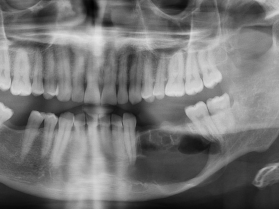

Parodontite

- Cause la plus fréquente de perte de dents

- Plaque dentaire > Gingivite > Destruction du ligament parodontal > Resorption osseuse

- Elargissement de l’espace du ligament parodontal

- Osteolyse

- Defaut de recouvrement des dents

Osteolyse (blanc), elargissement du ligament parodontal (noir)

Defaut de recouvrement dentaire